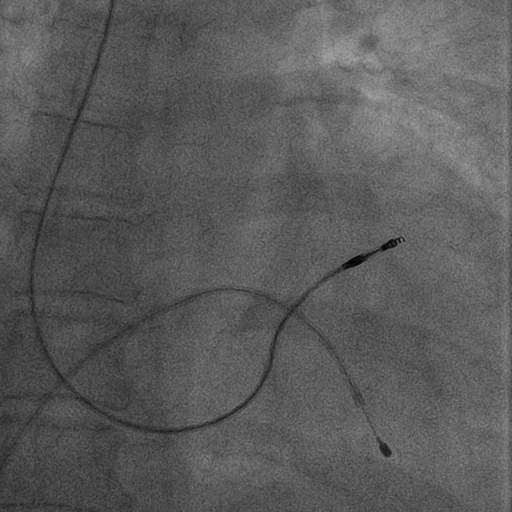

Venogram

• Difficult puncture

• Pre-existing leads

• 10-15 ml of contrast from ipsilateral arm

• Management of stenosis

Puncture with venogram